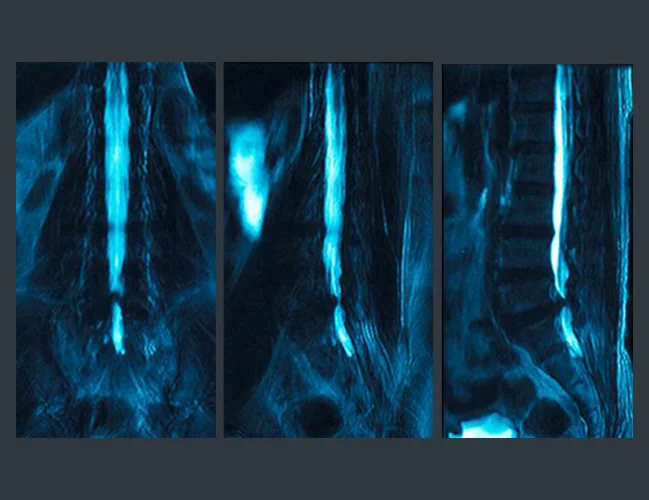

We go beyond masking symptoms. Using state-of-the-art diagnostics, including on-site digital X-rays, open MRI referrals, and Electromyography (EMG/NCS) testing, we pinpoint the exact source of your back pain and develop personalized back pain treatment plans. This evidence-based approach ensures effective care for both acute and chronic back pain while helping many patients avoid unnecessary surgery.

A herniated disc, also referred to as a slipped disc, ruptured disc, or disc herniation, is one of the most common causes of back pain. Often, people visit a spine specialist for back pain and unknowingly have a herniated disc. Herniated discs affect the vertebrae, the bones that make up your spine, and the spinal discs, which provide support and flexibility to your back.

Sciatica, or Lumbar Radiculopathy, is an irritation or compression of the sciatic nerve roots in the lumbar spine. Most commonly, sciatica causes lower back pain. Because the sciatic nerve roots in the lumbar spine extend to the hips, buttocks, legs and feet – an injury or irritation in the lumbar spine region of your back causes symptoms in these areas.

Spinal Stenosis is a condition of the spine that causes a narrowing of the spinal canal and compression on the nerves and spinal cord. This pressure and reduced space in the canal most commonly causes low back pain.

Degenerative Disc Disease is a condition that causes pain, most commonly lower back pain, due to degeneration of the discs in the spine. Degenerative disc disease is actually one of most common causes of lower back pain and often goes undiagnosed for a long period of time.